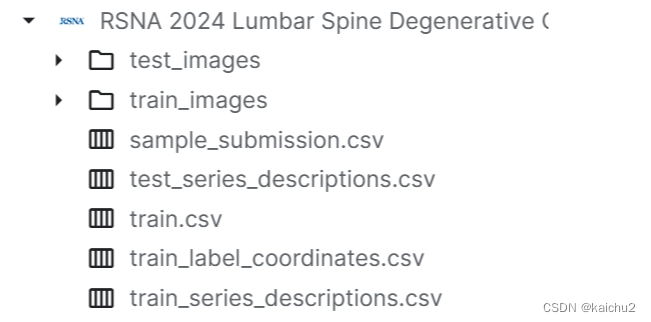

2、数据介绍

整体数据层级目录